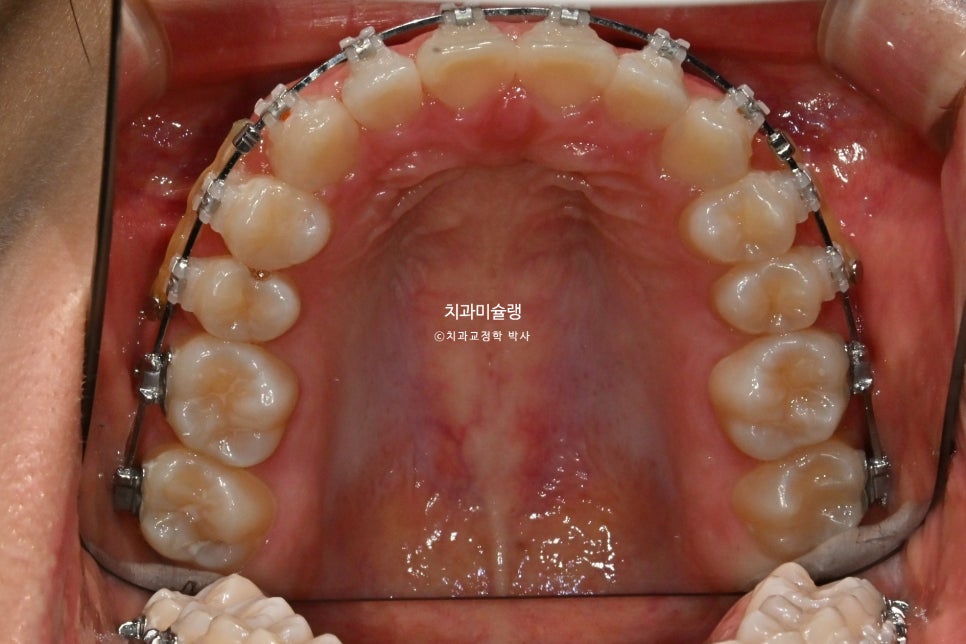

마무리 조절을 거쳐 2026년 3월, 치료를 마쳤습니다. 총 치료기간은 1년 2개월 입니다.

중심선은 정확히 맞으며 과개교합은 개선되었습니다. 브라켓 주변부 양치가 안되어 안타깝게도 충치가 좀 생겼습니다. 어금니 교합관계는 1급관계를 달성.

1년 2개월간 치근흡수는 없으며, 치근평행도는 좋습니다. 사랑니 공간으로 어금니들이 잘 이동하였습니다.